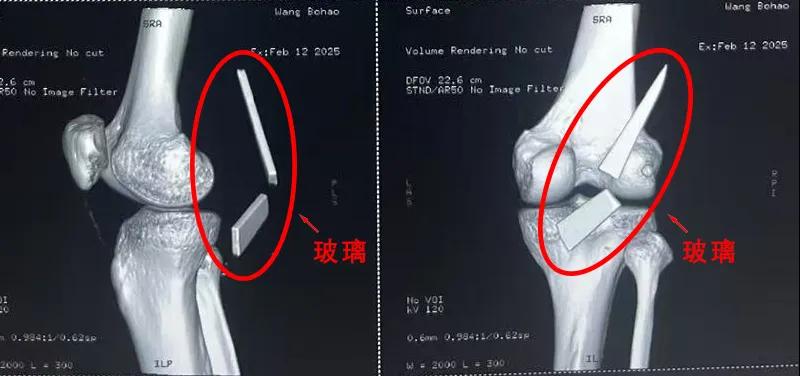

患者家屬這才開始意識到問題的嚴(yán)重性,便帶著孩子到鄉(xiāng)鎮(zhèn)衛(wèi)生院檢查——結(jié)果顯示右膝關(guān)節(jié)后方竟然殘留著兩塊兒鋒利的碎玻璃,測量后預(yù)估玻璃總長將近13厘米!

由于玻璃位置毗鄰坐骨神經(jīng)和股動脈,一旦刺破股動脈,將嚴(yán)重威脅生命。家屬著急萬分,想著能否盡快手術(shù)取出碎片,于是慕名來到漯河醫(yī)專二附院(漯河市骨科醫(yī)院、漯河市立醫(yī)院)手顯微外科(修復(fù)重建骨感染科)。

術(shù)中,馬廣輝醫(yī)生憑借扎實(shí)的理論知識和嫻熟的顯微外科技術(shù),順利找到深深刺進(jìn)肌肉的兩塊玻璃,肉眼可見玻璃尖端距股動脈僅有不到半公分的距離!如果患者再耽誤半天或者再多活動幾次膝關(guān)節(jié),小指粗的股動脈很有可能被玻璃扎破,后果難以想象。

最終,馬廣輝醫(yī)生在血管、神經(jīng)表面順利取出兩塊玻璃碎片,拆除了埋在患者膝關(guān)節(jié)的“炸彈”。在告知患者家屬術(shù)中情況后,家屬懸著的心終于放了下來。